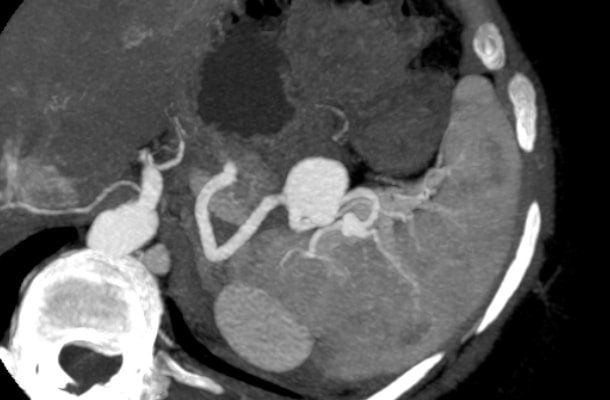

Аневризма селезенки (ААС) — это патология, которая выражается в деформации (выпуклости) стенок артерии в результате их истончения и растяжения, создавая в них полости, заполненные кровью.

Аневризмы можно обнаружить по-разному. Основные методы: рентген, УЗИ, МРТ, компьютерная томография.

Радиологическое обследование считается приоритетным методом диагностики, так как с его помощью можно наиболее точно определить размер аневризмы и ее расположение.